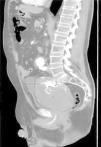

Presentamos el caso de un paciente de 71 años diagnosticado hace 2 años de aneurisma de aorta abdominal y aneurisma de arteria hipogástrica izquierda trombosado, realizando bypass aorto-aórtico y ligadura y exclusión del segundo. Un año más tarde, tras dolor en fosa ilíaca izquierda se descubre endofuga del aneurisma hipogástrico realizando cierre y embolización del saco mediante radiología intervencionista (coils y pegamento biológico), procedimiento que fue necesario repetir 8 meses después por el mismo motivo. Tres meses después, consulta en el servicio de urgencia, esta vez por clínica de estreñimiento, sin dificultad para eliminar gases por el ano y oliguria de 3 semanas de evolución, sin otra sintomatología. Al tacto rectal se palpa masa pélvica que comprime ampolla rectal en su cara anterior e izquierda, no pulsátil, sugiriendo compresión extrínseca, sin productos patológicos. En la radiografía de abdomen se aprecia leve dilatación de escasas asas de intestino delgado y colon hasta descendente. Se realiza ecografía y angio-TC describiéndose masa pélvica compatible con gran aneurisma trombosado de la arteria hipogástrica izquierda relleno de coils, que comprime recto y vejiga e hidronefrosis izquierda leve (fig. 1). Se interviene de forma programada, a través de incisión abdominal, retrayendo el peritoneo hasta alcanzar el retroperitoneo. Se realizó aneurismotomía con extracción y limpieza del contenido, así como sutura de un punto sangrante en el saco aneurismático (fig. 2). En el primer día postoperatorio, el paciente es reintervenido por sangrado en músculo psoas, realizando hemostasia. También se diagnostica tromboembolismo pulmonar que obliga a la colocación de un filtro temporal en la vena cava y anticoagulación con heparinas de bajo peso molecular. Posteriormente evoluciona favorablemente, siendo dado de alta.